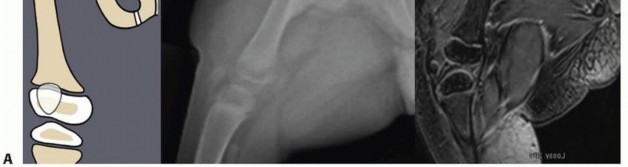

Illustration 3 for Treatment for Congenital Femoral Deficiency: What You Need to Know Illustration 4 for Treatment for Congenital Femoral Deficiency: What You Need to Know Illustration 5 for Treatment for Congenital Femoral Deficiency: What You Need to Know Illustration 6 for Treatment for Congenital Femoral Deficiency: What You Need to Know FIG 2 • A. Paley type 1b CFD (subtrochanteric type) shown by illustration, radiograph, and MRI. Note the nonossified subtrochanteric cartilage B. Paley type 1b CFD (neck type) shown by illustration, radiograph, and MRI. Note the nonossified neck. *